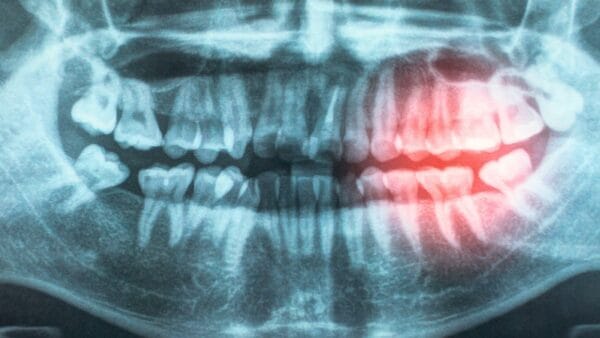

Como relatado na Scientific Reports, essa inovação pode acelerar significativamente as pesquisas relacionadas a doenças. Ela também oferece avanços promissores para diagnósticos médicos, permitindo, por exemplo, a detecção de câncer em imagens de biópsias em questão de minutos—uma tarefa que normalmente levaria várias horas para ser realizada por patologistas humanos.

A equipe então testou o modelo com imagens de outras pesquisas, incluindo estudos sobre câncer de mama e metástase em linfonodos. Eles descobriram que o modelo de IA não apenas identificou patologias com precisão e rapidez, mas também superou os modelos anteriores em velocidade. De forma notável, ele detectou casos que uma equipe de especialistas humanos treinados havia negligenciado.